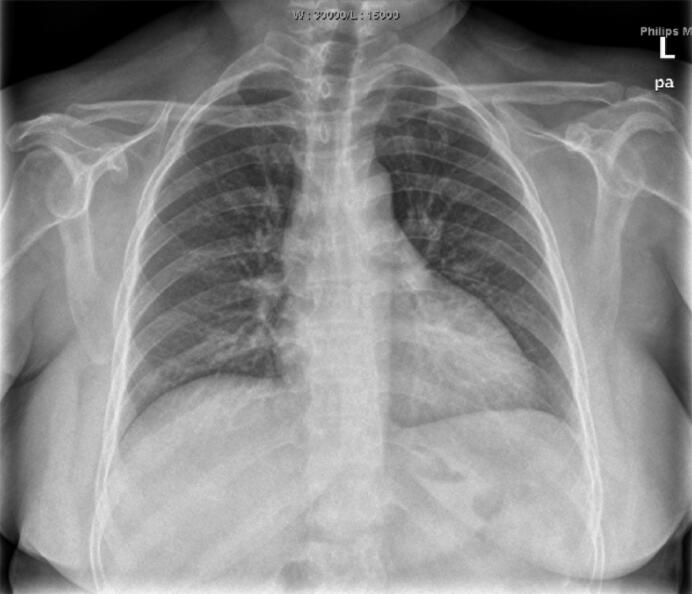

急诊生化:ALT710.7U/L,AST2585.7U/L;U REA4.9mmol/L,CREA97μmol/L,UA337μmol/L,K+3﹒54mmol/L。尿常规隐血+++。便常规无异常。血常规:WBC16.57×199/L,N89.9%。BNP>9000pg/ml,尿渗透压222mOsm/(kg•H2O)。凝血:D‐二聚体6593ng/ml,APTT58.9秒,PT 38﹒7秒。甲状腺功能:FT31﹒03pg/ml,T43﹒36μg/dl,FT40﹒388ng/dl,T30﹒408nmol/L,TSH0.12μIU/ml。血清泌乳素测定0.22ng/ml,血清促卵泡刺激素测定1.00IU/L,雌二醇测定15pg/ml,睾酮测定0.01ng/ml,孕酮测定0.15ng/ml,血清促黄体生成素测定0.19MIU/ml。皮质醇节律(0点、8点、16点):1002nmol/L、413.4nmol/L、1391nmol/L;ACTH(0点、8点、16点):74.1pg/ml、41.6pg/ml、47.2pg/ml。心电图检查见图1。心脏彩超:LVDd60mm,EF 46%,左心房、左心室增大,心包积液(少量)。胸片(2011‐7‐3)检查见图2。

图2 双肺纹理增多,心影增大

入院后于ICU予重症监护,抗感染、激素替代、多巴胺及多巴酚丁胺强心、升压以及维持水、电解质、酸碱平衡等对症支持治疗,以及气管插管呼吸机辅助通气、营养支持治疗。于6月30日患者出现2次室颤,经除颤、激素替代、纠正电解质紊乱等治疗均抢救成功。患者自主呼吸逐步恢复。于7月3日拔除气管插管。多次查脑钠肽>9000pg/ml。胸片提示心影明显增大。患者有甲状腺功能减退,但考虑患者急性心力衰竭很严重,ICU医师因担心补充甲状腺素后引起心功能恶化,转入CCU继续治疗。根据甲状腺功能调整糖皮质激素以及甲状腺素片用量,根据血压情况调整降压用药,因此类患者易发生栓塞事件,予低分子肝素抗凝治疗。患者病情逐步稳定。2011‐9‐13复查心脏彩超:LAD40mm,LVDd50mm,EF 55%。左心房、左心室稍大;左心室舒张功能减退。出院后2011年11月复查胸片见图3。

患者的心力衰竭为长期甲状腺功能减退引起甲状腺功能减退性心脏病所致。感染诱发心力衰竭急性发作。甲状腺功能减退性心脏病是由于甲状腺素合成、分泌不足或生物效应不足而引起心肌收缩力减弱,心排血量和外周血流量减少等引发的一系列症状和体征的内分泌紊乱性心脏病。因甲状腺本身疾病引起的功能减退称原发性甲状腺功能减退或甲状腺性甲状腺功能减退,占甲状腺功能减退的90%~95%。缘于垂体及下丘脑病变的甲状腺功能减退系中枢性甲状腺功能减退或继发性与三发性甲状腺功能减退。该患者属席汉综合征继发性甲状腺功能减退。治疗主要是控制急性心力衰竭的同时补充糖皮质激素及甲状腺激素。甲状腺功能减退所致心脏扩大,治疗主要以补充甲状腺素为主,随着甲状腺功能逐渐恢复,心脏也会逐渐回缩,该患者出院后仍坚持服用甲状腺激素,心功能保持良好,复查胸片心影已恢复正常大小。